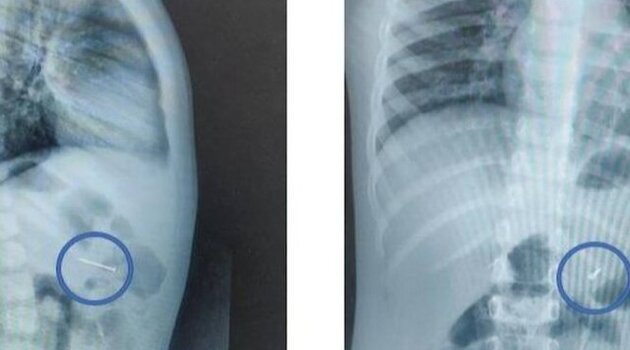

Подмосковные врачи спасли мальчика, проглотившего гвоздь